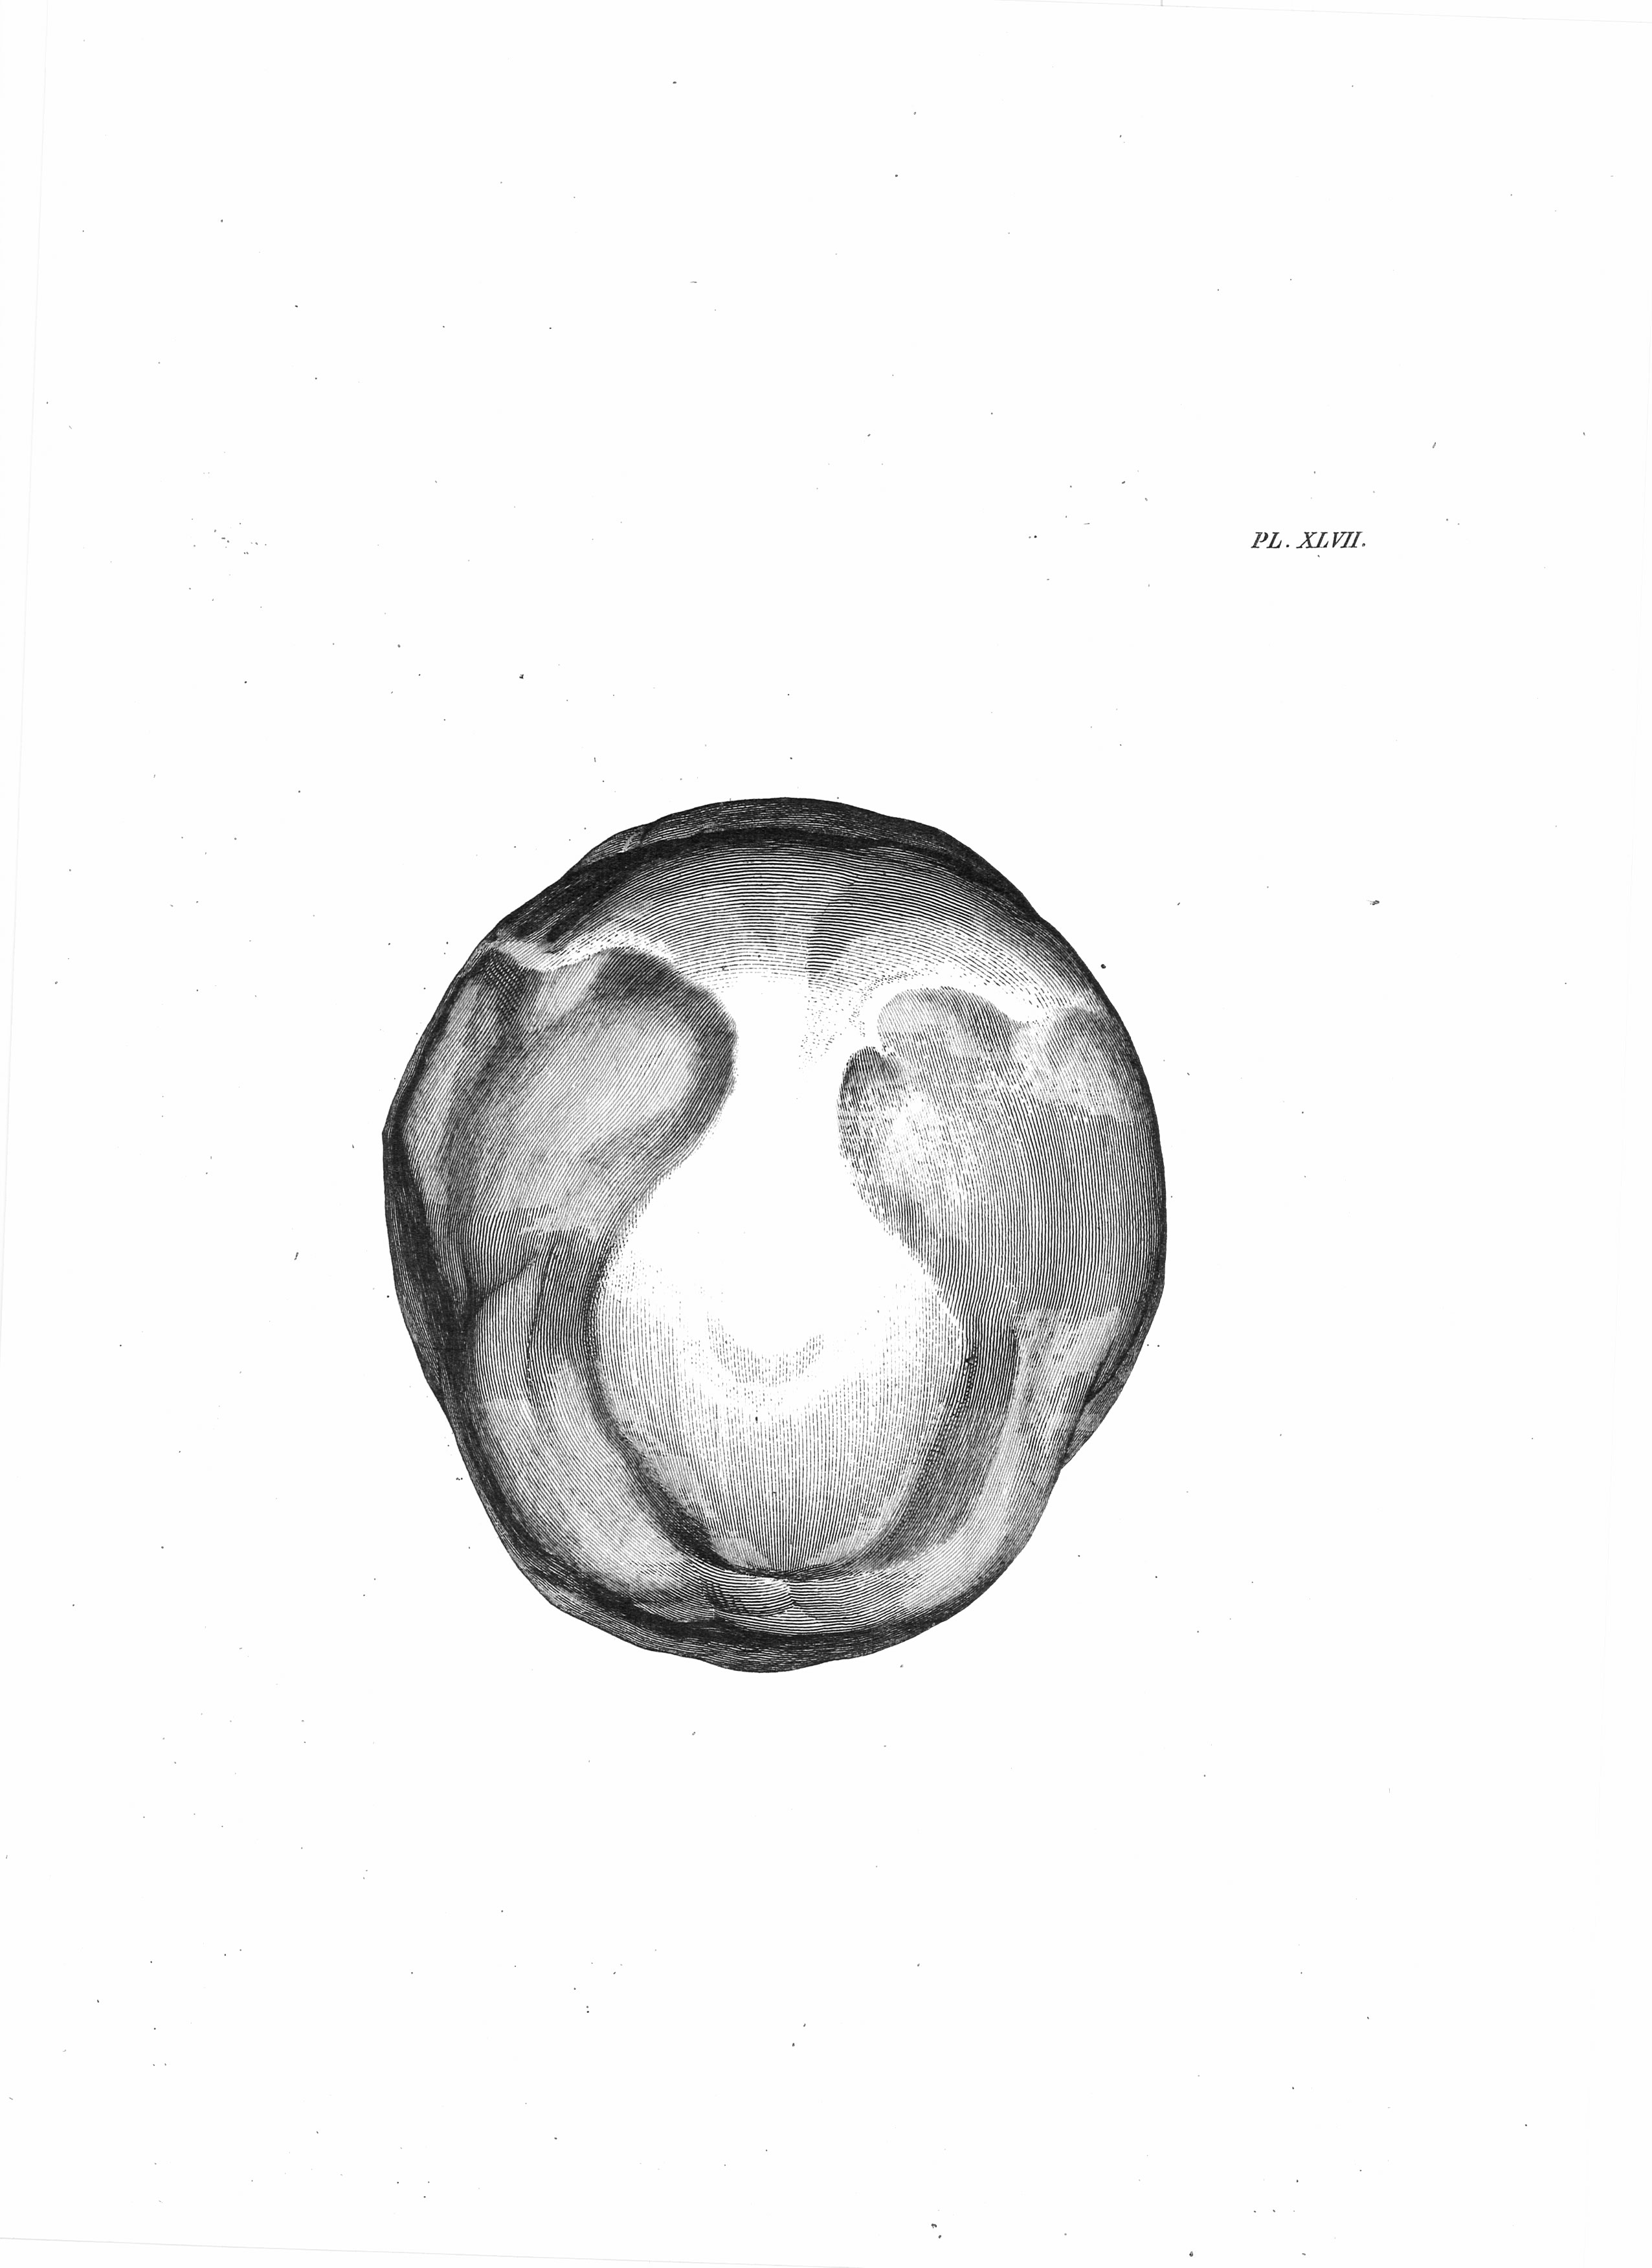

Gall, F. J. (1818). Anatomie et physiologie du système nerveux en général, et du cerveau en particulier, Avec des observations sur la possibilité de reconnoître plusieurs dispositions intellectuelles et morales de l´homme et des animaux, par la configuration de leurs têtes.

Librairie Grecque-Latine-Allemande, Vol. 3, I-XXXV u. 1-379 100 planches.